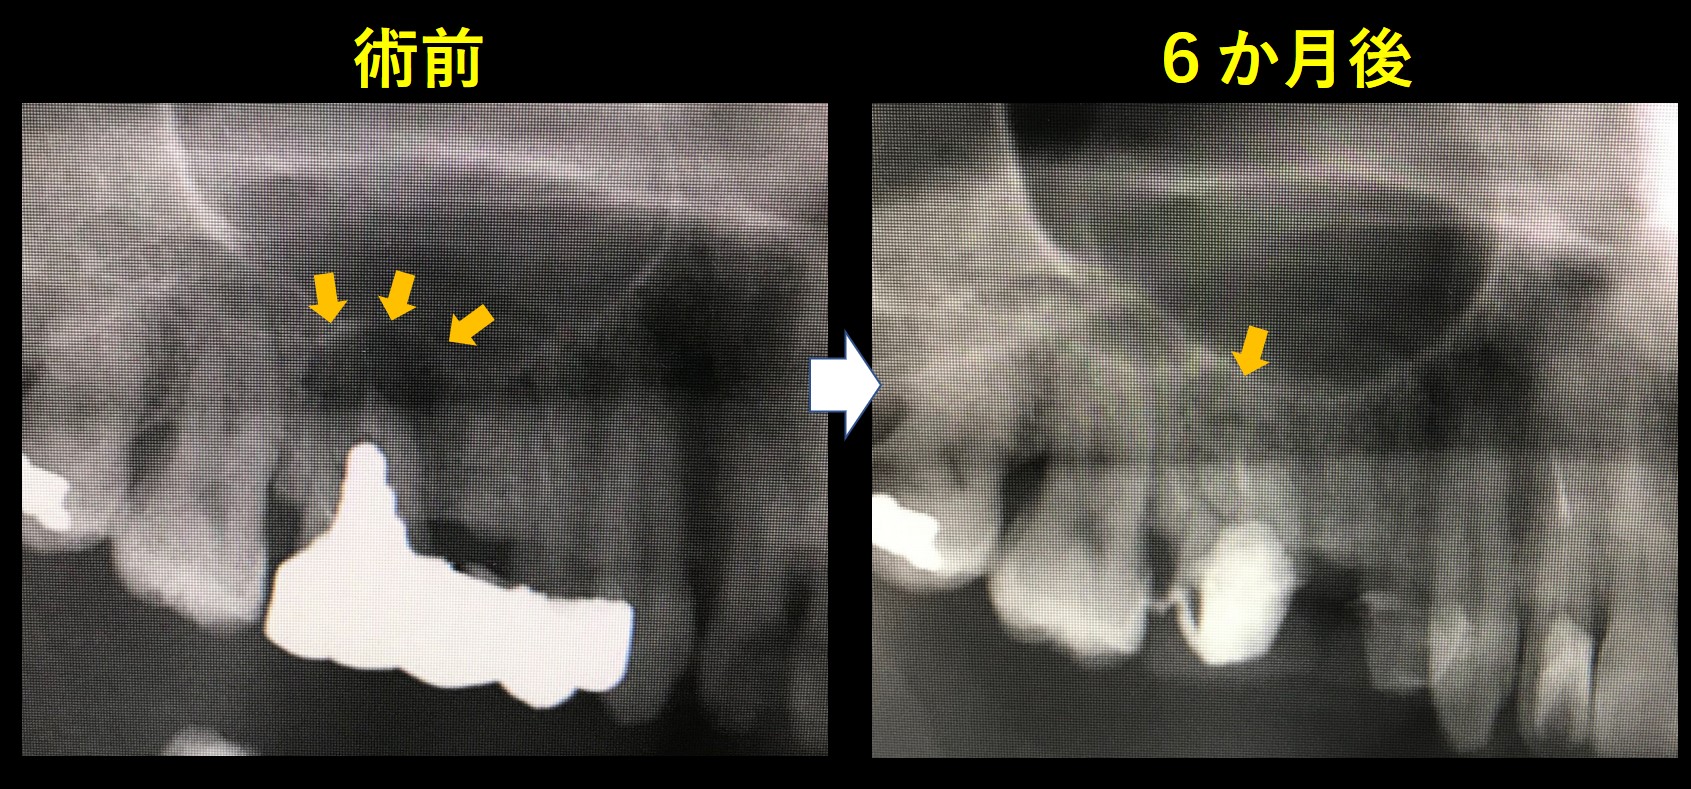

← 246.根管治療